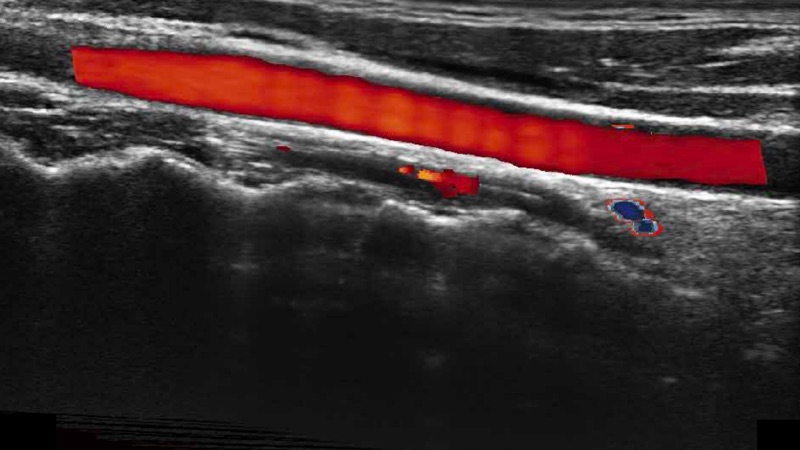

高分辨率血流成像技術(shù)提高了對(duì)低速血流信號(hào)的檢測(cè)能力。在提高空間分辨率的同時(shí),也克服了血流外溢現(xiàn)象,為用戶提供更加真實(shí)的血流動(dòng)力學(xué)信息。

通過(guò)色彩血流和實(shí)時(shí)寬景相結(jié)合,可觀察到完整的靜脈或動(dòng)脈的血流,方便醫(yī)生檢查。實(shí)時(shí)掃查過(guò)程中,如有任何操作失誤也可以很容易地進(jìn)行回掃擦除,而不會(huì)中斷掃查。